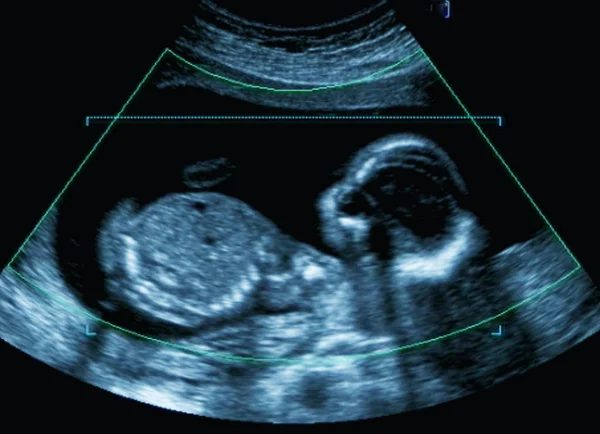

In Italia l’aborto è praticato ancora illegalmente. Era il 22 maggio 1978 quando il Parlamento approvò la Legge 194, che disciplina l’interruzione volontaria di gravidanza (IVG) e la tutela sociale della maternità. Consente l’aborto entro i primi 90 giorni per motivi di salute, economici, sociali o familiari, e successivamente solo per motivi terapeutici, garantendo il diritto alla salute della donna e l’obiezione di coscienza per il personale sanitario.

Noi del Comitato “Pro-life insieme“ non facciamo una guerra santa, e non paragoniamo l’aborto all’omicidio. Il discorso è scientificamente inappellabile: l’aborto è realmente un omicidio, visto che il 96% dei biologi mondiali pone l’inizio della vita umana dal concepimento; visto che il cuore batte dal 16mo giorno; visto che una donna solitamente attende un bambino e non una pianta o un sasso.